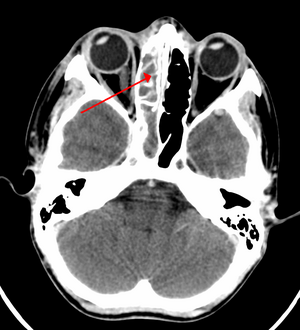

A CT scan showing sinusitis of the ethmoid sinus